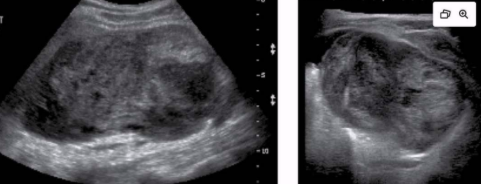

Abscess

Caused by cuts, scrapes, crushing injuries, surgical trauma, etc.

Abdominal wall abscesses are usually a surgical complication

Clinical presentation - redness, pain, swelling, elevated WBC (AKA leukocytosis)

US appearance:

Heterogeneous

Hypoechoic fluid w/ echogenic debris

Irregular borders

Posterior enhancement

Peripheral hypervascularity